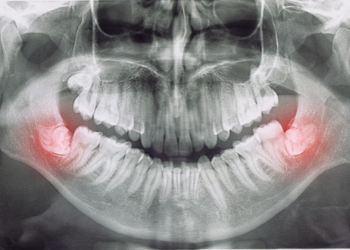

Wisdom Teeth Extraction

Wisdom teeth are also known as third molar teeth. They begin to emerge in the back of the upper and lower jaws, usually between the ages of 17 and 25 but have been known to show up for some people in their 40s or 50s!

For many people, wisdom teeth do not fully emerge, so many people feel extraction is not a necessary process. However, these unseen teeth can become impacted against adjacent molars or against your jaw. Our team can help assess your wisdom teeth to see if extraction is necessary.